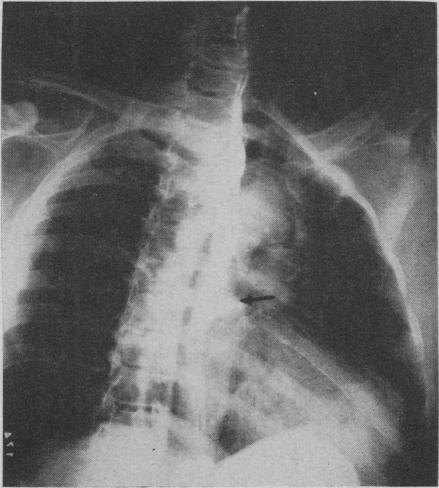

Diverticula of the oesophagus.

Can Med Assoc J. 1957 May 15;76(10):822-31.